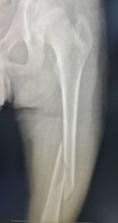

股骨干骨折彈性髓內(nèi)釘固定術(shù)前

股骨干骨折彈性髓內(nèi)釘固定術(shù)后